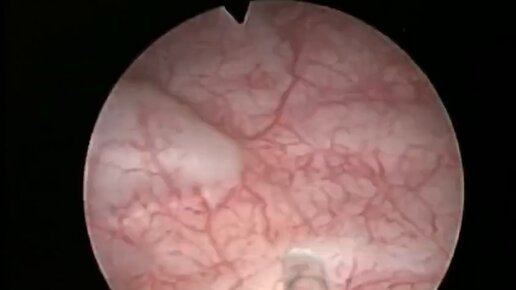

Цистоскопия. Удаление лейомиомы мочевого пузыря

Денис Давыдов врач-уролог, онкоуролог